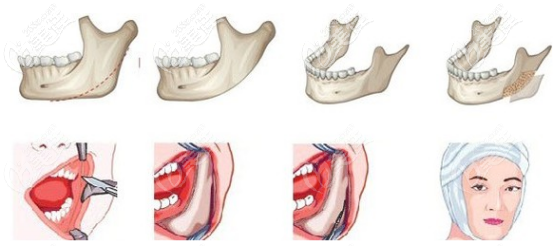

很多脸型方正的人都想通过下颌角削骨手术变成小V脸,不知道做长曲线下颌角截骨手术除了改变脸型的同时能缩短下巴吗?手术有没有什么后遗症呢?今天我们就来了解一下吧。